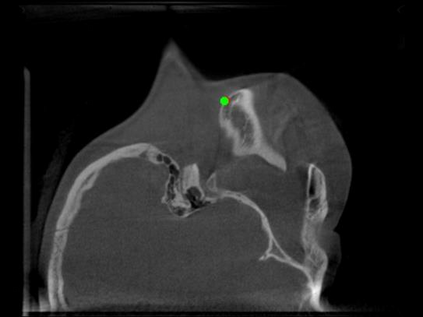

Detecting 3D landmarks on cone-beam computed tomography (CBCT) is crucial to assessing and quantifying the anatomical abnormalities in 3D cephalometric analysis. However, the current methods are time-consuming and suffer from large biases in landmark localization, leading to unreliable diagnosis results. In this work, we propose a novel Structure-Aware Long Short-Term Memory framework (SA-LSTM) for efficient and accurate 3D landmark detection. To reduce the computational burden, SA-LSTM is designed in two stages. It first locates the coarse landmarks via heatmap regression on a down-sampled CBCT volume and then progressively refines landmarks by attentive offset regression using multi-resolution cropped patches. To boost accuracy, SA-LSTM captures global-local dependence among the cropping patches via self-attention. Specifically, a novel graph attention module implicitly encodes the landmark's global structure to rationalize the predicted position. Moreover, a novel attention-gated module recursively filters irrelevant local features and maintains high-confident local predictions for aggregating the final result. Experiments conducted on an in-house dataset and a public dataset show that our method outperforms state-of-the-art methods, achieving 1.64 mm and 2.37 mm average errors, respectively. Furthermore, our method is very efficient, taking only 0.5 seconds for inferring the whole CBCT volume of resolution 768$\times$768$\times$576.